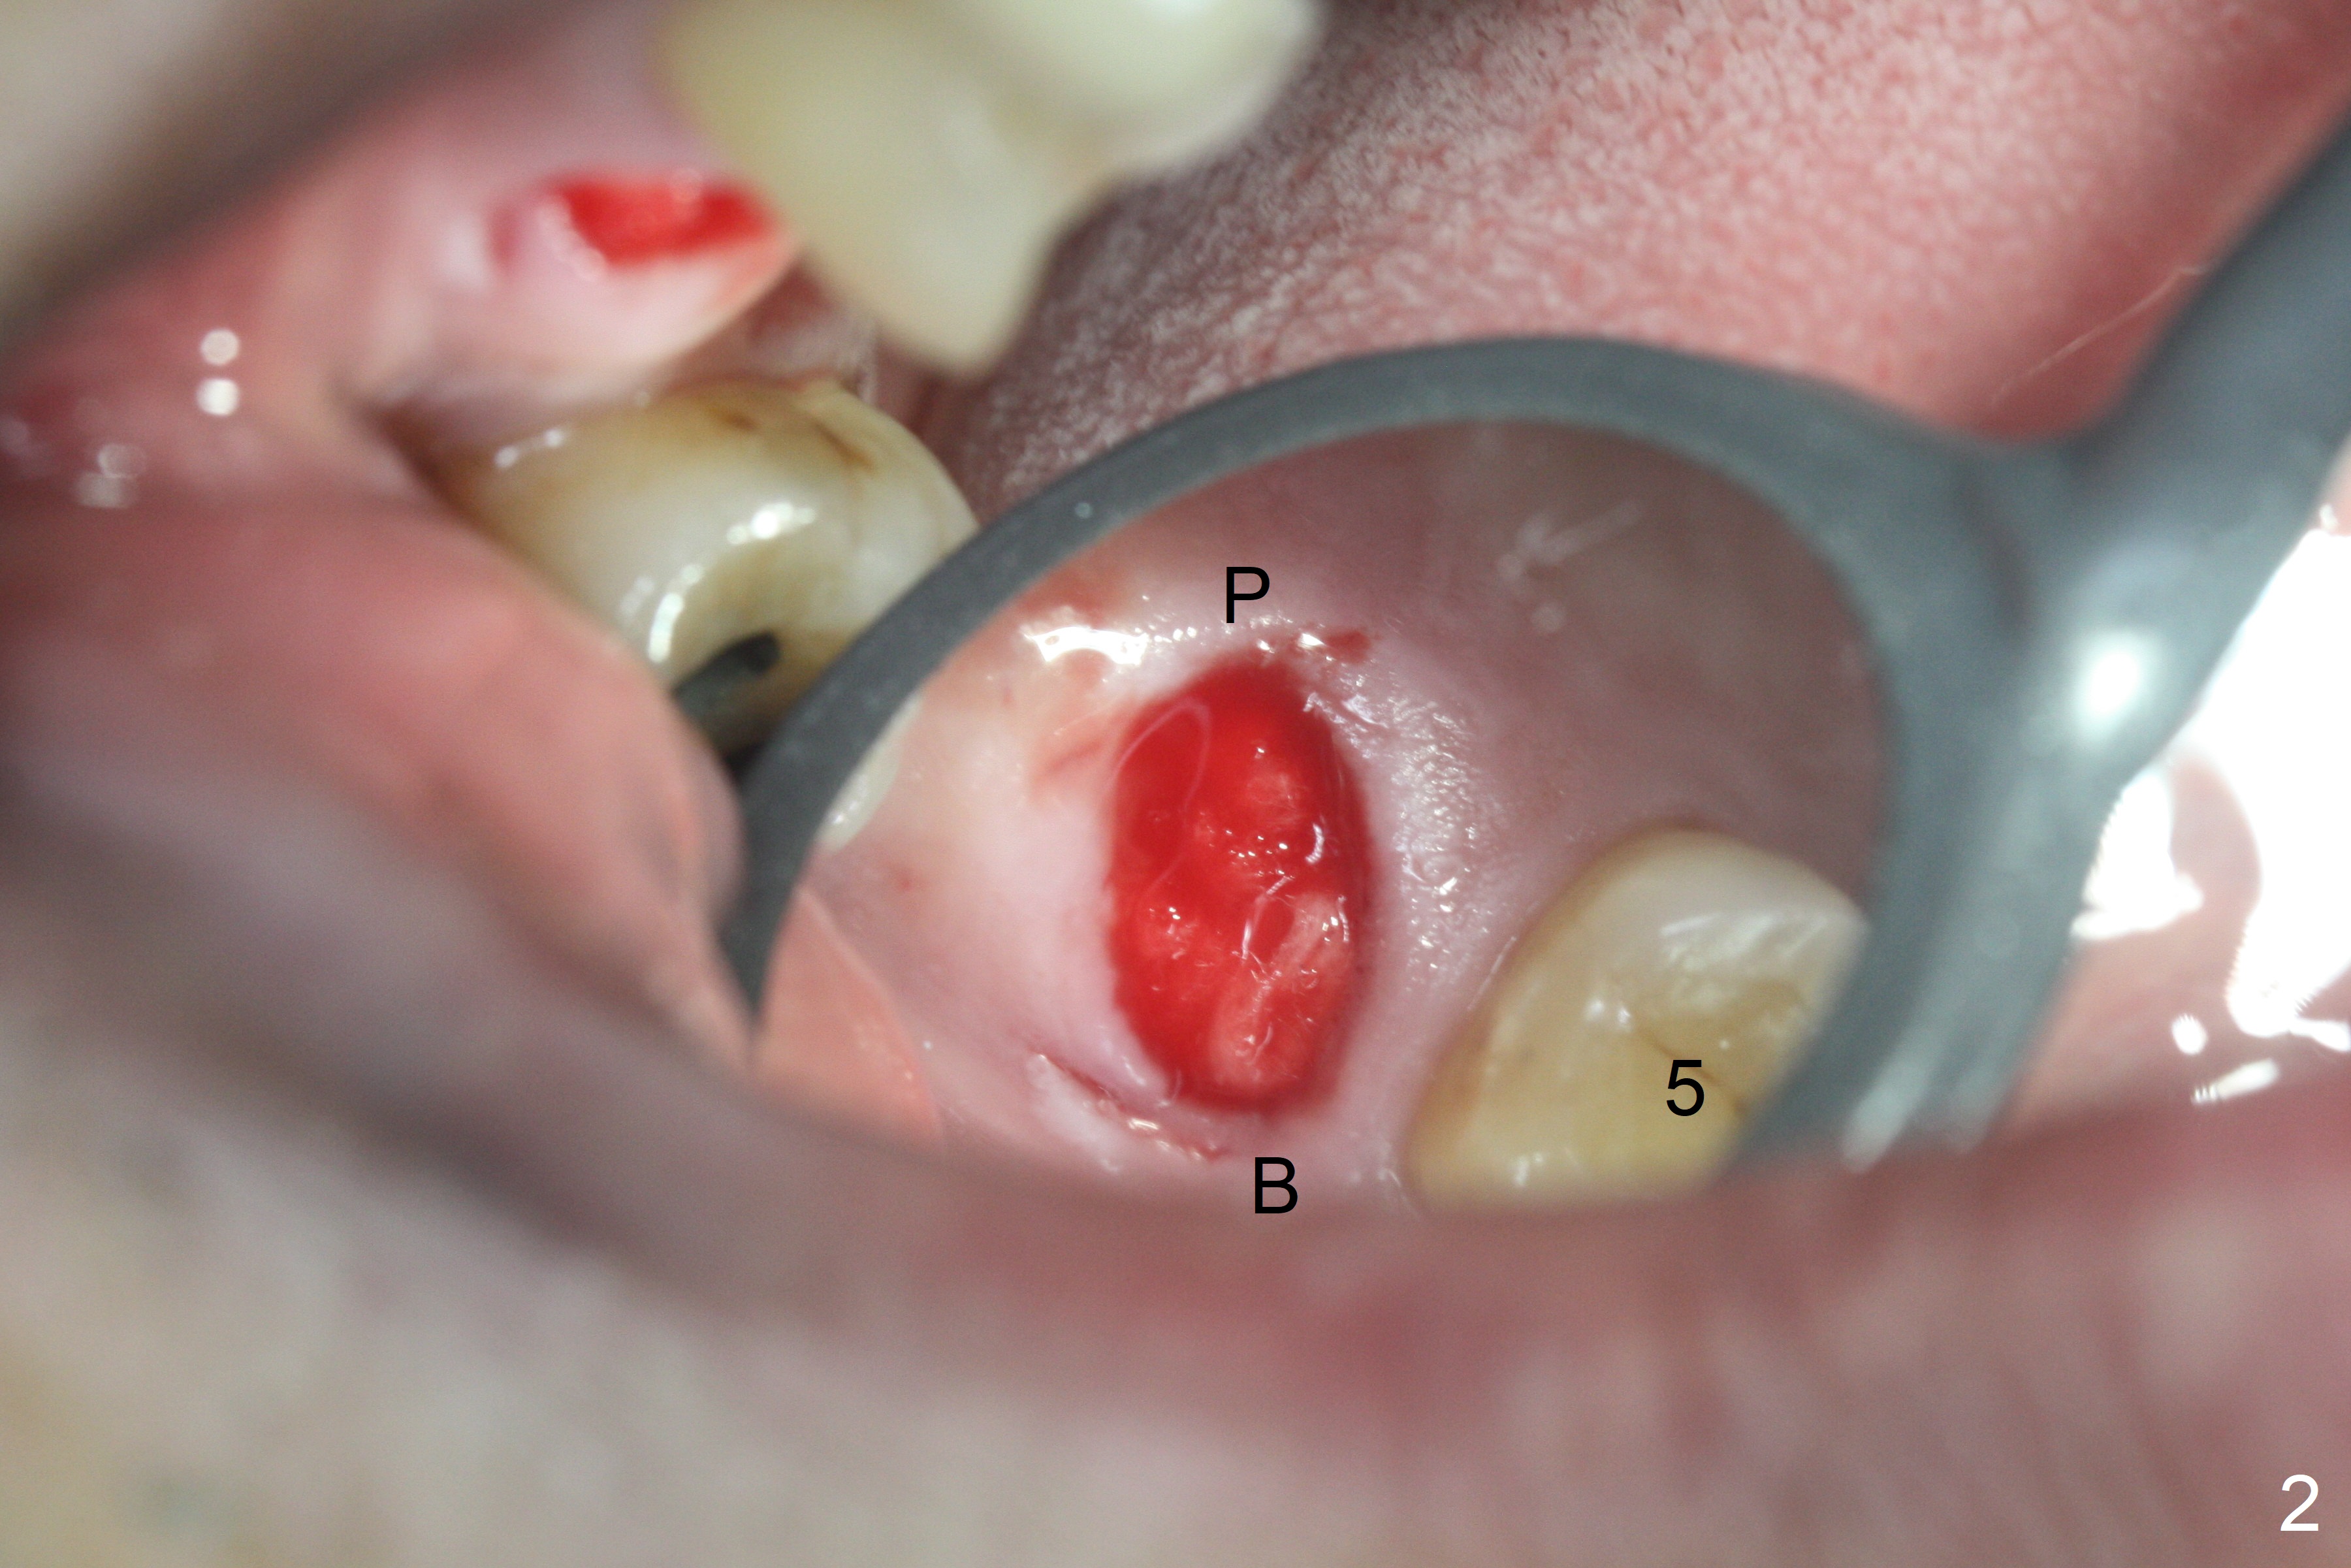

The palatal cusp of the affected 2nd premolar is apparently rotated distal (Fig.1). It is more obvious for the socket (Fig.2): the palatal (P) portion of the socket is more distal than the buccal (B) one. When the gauze is removed (Fig.3), Lindamann bur is used to remove the disto(D)palatal bone of the socket (data not shown), followed by starter drill in the DP wall obliquely (Fig.3'). Once the drill enters the bone for 1-2 mm, the bur is straightened and pushed slightly distal (Fig.3''). Fig.4 shows a parallel pin distal (overcorrect) to the original socket (Fig.4 red dashed line). Sequential osteotomy is conducted until 3.8x13 mm drill for 18 mm (Fig.5): note the 2 steps of the osteotomy (red lines). Since the apical portion of the osteotomy is larger than the drill, a larger implant than expected (5x16 mm) is placed. The implant ends up in the middle of the edentulous area (due to the stepped osteotomy; Fig.6-9; >60 Ncm). Vera allograft is placed (Fig.7-9 *) prior to and after placement of a 6.5x4(3) mm abutment (Fig.8-10). The remaining socket opening is sealed with a piece of Collagen plug (Fig.10 *). The socket is then closed by an immediate provisional (Fig.11 P). The abutment is retightened 2 months postop (Fig.12,13). The crown is cemented 4.5 months postop. Panoramic X-ray and CT are taken nearly 7 months post cementation (Fig.14,15) when the patient is ready for #30 implant guide preparation.